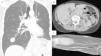

The patient remained asymptomatic and disease-free until 16 months after the intervention, when multiple nodules consistent with metastases were detected in the lungs, pleura, liver, bone, and muscles (Fig. 1).

(A) Chest computed tomography, showing a 25-mm nodular image in the basal segment of the right lung field. (B) Tomography slice of the abdomen, showing a mass in liver segment V, measuring approximately 30mm. (C) Magnetic resonance image of nodular formation located between the muscle planes of the palm and distal third of the right forearm, 50mm×30mm×20mm.